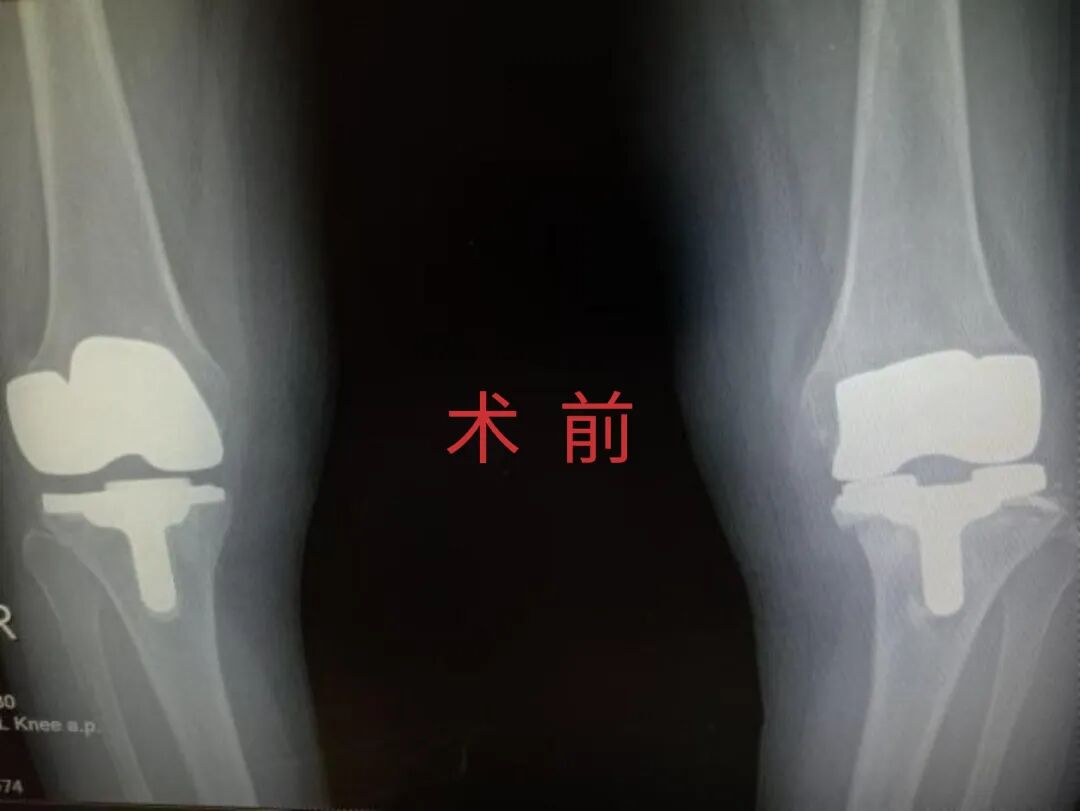

为提升区域内基层医疗机构糖尿病足诊疗服务能力、促进青年医师对糖尿病足的规范化诊治水平,遵义市第二城市医疗集团总院(贵州航天医院)圆满举办贵州省继续医学教育项目——胫骨横向骨搬移技术治疗糖尿病足专题研讨班。 贵州航天医院党委委员、副院长彭亮出席会议并致辞,遵义市第二城市医疗集团各成员单位,以及红花岗区、汇川区、绥阳县、桐梓县等多个区县的基层医疗机构骨干医师参加会议。 研讨班 本次研讨班以胫骨横向骨搬移技术在糖尿病足治疗中的应用为核心主题,围绕糖尿病药物治疗与生活方式管理策略、围手术期血糖精准调控要点、胫骨横向骨搬移技术典型病例深度解析、糖尿病足的临床分型与个体化治疗方案制定等临床实践中的热点与难点展开深入探讨,通过专题授课、案例研讨、互动交流等多元化形式,为参会者搭建了理论与实践结合的学习平台。 此次研讨班不仅为区域内基层医院搭建了学术交流与经验共享的平台,更对推动糖尿病足预防、诊断与治疗的规范化、系统化发展起到了积极作用,有效助力青年医师更新专业知识体系、提升临床技能,为进一步保障区域内糖尿病足患者的健康奠定了坚实基础。 贵州航天医院骨科专家简介 陈明勇 骨一科主任,副主任医师 临床擅长:从事创伤骨科工作约20年,对骨缺损、骨不连、骨肿瘤、肢体畸形等的肢体矫形重建及功能重建,慢性化脓性骨髓炎的根治治疗、糖尿病足的保肢治疗、快速康复理念(ERAS)下的老年骨折的诊治,四肢复杂骨折的诊治,四肢骨折等微创手术治疗具有丰富的临床经验。 2004年毕业于遵义医学院临床专业,曾在中国人民解放军总医院、广西医科大学第一附属医院、上海第六人民医院骨科进修。中国中西医结合学会骨伤科专业委员会横向骨搬移治疗糖尿病足及微血管网再生学组首届委员,遵义市医学会创伤分会常务委员。 瞿 晖 骨科党支部书记,骨二科主任,副主任医师 临床擅长:对骨科的常见病、关节外科、脊柱外科及运动医学疾病的诊治具有丰富的临床经验,熟练掌握骨科手术操作技术。 毕业于遵义医学院临床医学系,2005年前往广州中山大学第一附院骨显微医学部进修学习,2011年前往成都华西医院进修学习,并多次在省内外学习骨科相关知识,是中华医学会骨科分会会员。 赵小锋 中共党员,骨二科副主任,副主任医师 临床擅长:从事骨科临床工作11年,对骨科常见病、多发病诊疗有较为丰富的临床经验,擅长脊柱相关疾病诊断及治疗,尤其是颈、腰、腿疼痛疾病诊断及治疗,擅长胸腰椎骨折微创经皮穿刺内固定术、经皮穿刺椎体成形术、经皮穿刺脊柱内镜下腰椎间盘摘除术、单纯开创腰椎间盘摘除术、腰椎滑脱复位椎间植骨椎融合内固定术、腰椎管狭窄减压融合内固定术及人工髋、膝关节置换术等。 2012年毕业于遵义医学院外科学专业硕士研究生,2019年参加“遵义市115医学人才精英计划”于上海交通大学第一附属医院培训学习,2023年于北京大学第三人民医院脊柱外科进修学习,曾获得遵义市优秀医师荣誉称号。 遵义市手外科第一届委员,遵义市医学会创伤分会第一届委员,遵义市医学会创伤分会第二届委员,贵州省康复医学会第三届脊柱脊髓专业会委员,遵义市医学会烧伤与整形外科学分会委员,发表论文5篇,其中国家级核心期刊1篇,SCI论文1篇,主持市级课题1项并结题,参与市级课题2项。 赵兴东 骨科主任医师 临床擅长:擅长骨科的常见病及各种创伤、四肢骨折创伤修复、骨感染、手足疾病的诊治和手足体表畸形的矫形整复,熟练掌握骨科四肢骨病及创伤的手术操作技术,尤其在四肢关节复杂性损伤、手足外伤、组织缺损创面、难治创面的皮瓣修复方面及平足、高弓足矫形方面及四肢慢性疼痛诊治、康复方面具有丰富的临床经验。 硕士研究生,毕业于遵义医学院临床外科系,2015年前往山东省立医院手足外科进修学习;遵义市医学分会创伤分会第一、二届委员,遵义市手外科医学会第二委届员会常务委员;在省级及省级以上期刊发表文章9篇,参编著作2部,参与主持并完成市级课题1项,参与市级课题2项、省级课题1项。 张艳金 中共党员,骨科副主任医师 临床擅长:从事骨外科工作16年,对复合伤、多发伤的救治、四肢骨干骨折、关节周围骨折、骨肿瘤、骨髓炎等诊治具有丰富的临床经验。 中共党员,硕士研究生,2006年本科毕业于山西医科大学第二临床医学院,2011年研究生毕业于北京军区总医院;在“老年COPD患者合并髋部骨折的诊治”国际合作课题组研究两年,在老年髋部骨折的诊治方面具有丰富的经验,并发表论文6篇;主持遵义市级课题1项,承担遵义医科大学的临床教学工作,获得遵义医科大学优秀带教老师荣誉。编撰有《骨科疾病诊疗精粹》一书,开展2项新技术,编撰地方规范《务川自治县创伤骨科常见疾病诊疗规范》一书。 张俊凯 骨科副主任医师 临床擅长:从事骨科临床工作28年,对创伤骨折、骨感染、骨缺损、骨不连等外科诊治,四肢骨折的微创手术治疗,四肢复杂骨折(如关节内粉碎性骨折、多发骨折等)的损伤控制及手术治疗等具有丰富的临床经验。 1995年毕业于遵义医学院临床专业,2009年前往复旦大学附属医院骨科进修1年。 卢懿明 中共党员,骨科副主任医师 临床擅长:从事骨科工作18年,对创伤骨折、四肢骨折的微创手术治疗、四肢复杂骨折(如关节内粉碎性骨折、多发骨折等)的损伤控制及手术治疗,尤其是髋部骨折的PFNA等微创技术,踝关节骨折、膝关节周围骨折的Mipo微创技术等具有丰富的临床经验,开展了4项新技术,发明6项新型专利技术。 2005年毕业于遵义医学院临床专业,2017年,前往南方医科大学第三附属医院骨科进修半年,回院后运用Mipo技术对骨干骨折及干骺端骨折的治疗技术,同时积极开展骨盆骨折、髋臼骨折腹直肌外侧切口的应用;发表了多篇专业论文,经常参与省内外学术交流会授课,获得医院荣誉称号多个。 邬夏荣 骨科副主任医师 临床擅长:从事骨科工作16年,对四肢复杂骨折、骨肿瘤的诊治,尤其是足踝创伤、慢性踝关节损伤、平足症等诊疗具有丰富的临床经验。 2006年毕业于遵义医科大学临床医学专业,曾在陆军军医大学西南医院进修学习,发表多篇骨科学术论文。 余德怀 中共党员,骨科副主任医师 临床擅长:从事骨科工作10余年,对运动医学、骨关节、脊柱外科常见病、多发病的诊治具有丰富的临床经验。 硕士研究生,2011年毕业于遵义医学院临床医学专业,曾前往遵义医科大学附属医院运动医学专业进修学习;是贵州省医学会运动医学分会青年委员,西部关节镜联盟委员;发表多篇骨科学术论文。 冯 乾 骨科副主任医师 临床擅长:从事骨科工作近20年,熟练掌握骨科多发病及常见病的诊治,尤其对脊柱退变性疾病的诊断及治疗具有丰富的临床经验,主要研究脊柱微创相关治疗方式,能熟练开展椎间孔镜及UBE。 曾前往北京大学第三医院进修学习疼痛及椎间孔镜、首都医科大学友谊医院专业进修脊柱内镜;是贵州省康复医学会第三届脊柱脊髓专业委员会委员;发明专利3项、发表脊柱外科专业论文多篇。 贵州航天医院骨科简介 基本情况 贵州航天医院(原3417医院)骨科组建于1968年,前身是以创伤和断肢(断指)再植闻名于世的上海市第六人民医院骨科,中国断肢(断指)再植的奠基者、中科院院士陈仲伟等专家莅临科室指导医疗和教学,并在70年代开展了贵州省首例断肢(断指)再植手术。组建50余年来,诊治患者已逾百万,挽救了无数的伤病员,成为了保障遵义地区人民群众健康的重要支撑。 经过几代人的不懈努力,今天的骨科,已由创伤骨科发展至骨病、骨肿瘤、骨结核等领域,现有脊柱外科、关节外科、四肢创伤、手足外科四个亚专科,成为了集医疗、教学、科研于一体的综合学科,是贵州省临床重点专科、遵义市临床重点专科、遵义市骨科临床医学中心、遵义市基层骨科专科联盟理事长单位。 科室目前开放床位110张,共有医护人员50余人,副高级以上专家18人,硕士研究生15人。拥有一流骨科医疗设备多台,每年不定期选派优秀技术骨干到全国各大知名医学院校进修、学习、参观、交流,并邀请国内、国外知名专家教授来院进行交流、指导,通过不断引进国内外先进的诊疗技术,科室医疗技术水平稳步提升,为广大人民群众提供了优质的医疗服务。 专科特色 骨一科 (一)骨缺损、骨不连的肢体与功能重建 胫骨横向骨搬移技术治疗糖尿病足: (二)慢性骨髓炎的根治治疗 (三)肢体缺血性疾病如糖尿病足、脉管炎的保肢治疗 (四)皮瓣修复 (五)复杂创伤的治疗 (六)老年髋部骨折及小儿骨折快速手术 老年髋部骨折: 骨二科 (一)胸腰椎骨折微创经皮椎弓根螺钉固定术 (二)老年性骨质疏松性患者腰椎滑脱脊柱内固定术(骨水泥螺钉) (三)V形双通道脊柱内镜技术(VBE)腰椎融合术治疗腰椎退行性疾病 (四)老年性骨质疏松性骨折(PVP/PKP)术 (五)人工髋关节置换术 (六)双侧股骨头坏死人工全髋关节置换 (七)右侧全髋置换术后假体周围骨折翻修 (八)人工膝关节置换术 (九)人工膝关节假体松动翻修 (十)关节镜技术 传统手术切口 关节镜技术切口 诊疗范围 骨一科 1.四肢创伤、矫形。 2.手、足踝外科。 骨二科 End